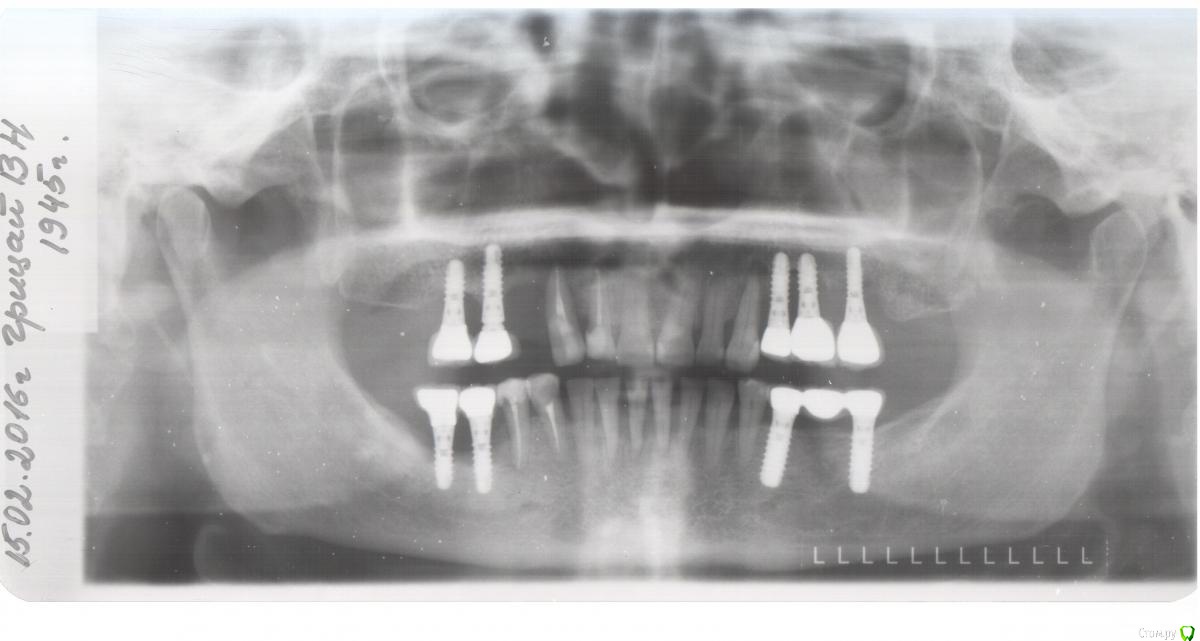

alekszander Опубликовано 25 февраля, 2016 Поделиться Опубликовано 25 февраля, 2016 Пациентка 45-го г.р. Из анамнеза: имплантация была проведена более 10 лет назад. Имплантаты на тот момент очень популярные и ставил человек минимум КМН на тот момент, а может уже и выше. Со слов пациентки - имплантат 1.4 закачался и выпал несколько недель назад. Пациентка никаких болей не отмечает. Общее соматическое состояние - удовлетворительное. Сахар на границе +- от нижней нормы, но диабет не ставят. Были проблемы с щитовидной железой (что точно не помнит), насколько понял из анамнеза - тиреоидит вроде. Когда-то была язва (более 20 лет назад) Не курит, не пьет. В целом жизнерадостная женщина и даже не выглядит на свой возраст. Вопрос как так? В 3-м квадранте все гуд, в остальных такая опа. Со стороны полости рта - имплантаты покрыты слизистой до уровня МК коронок. На момент обращения при пальпации обильное гнойное отделяемое, но болевых ощущений нет! Назначил АБ+НПВС+АГ+ХГ местно. Сегодня пришла: гной сохранен только в области 2.3,2.4,2.5,2.6 но уже скудное отделяемое. Пальпация по прежнему безболезненная. Слизистая без грануляций, розового цвета (поверхностно) Из вариантов - по хорошему: на выход имплантаты 1,2,4 квадранты+зубы 1.3,2.3. Временные съемные. Общий анализ крови и совместное наблюдение с эндокринологом. По поводу повторной имплантации чет- сомневаюсь, но нужны будут анализы. По плохому (умаляет пациентка,т.к возраст уже такой, что повторно не готова а съемное не хочется) сохранить имплантаты и диспансерное наблюдение. Правда тут у меня вопрос в голове, а что делать с 1.4,1.3,2.3 в плане протезирования?.... Коллеги прошу помощи, ситуация не однозначная. Прилагаю ОПТГ через год после протезирования и 2 недельный снимок. Ссылка на комментарий